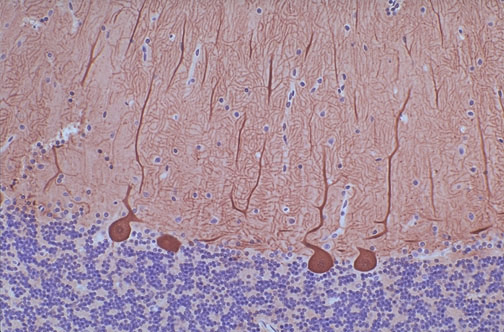

| This is the cerebellum, with the dark blue cells forming the granule cell layer below and the molecular layer above, with large Purkinje cells in between that are staining positively with antibody to calbinden with this immunohistochemical stain. Calbinden (a calcium binding protein) is found in neuronal cells. |